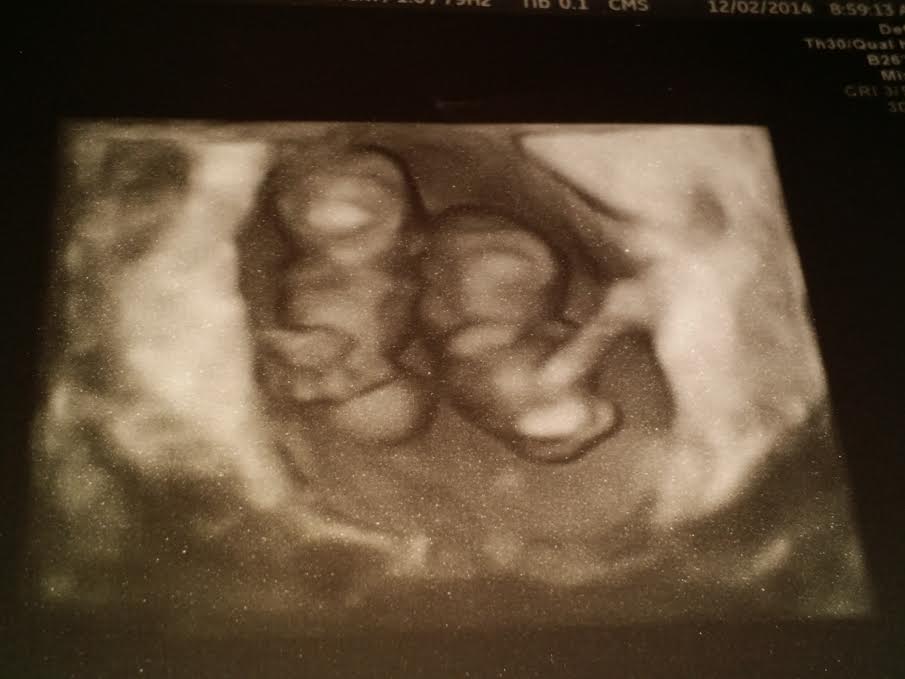

I was so anxious to go today's ultrasound. I just found out via ER sono tech last week I was having twins after being told twice there was only one on two different ultrasounds at 5w5d and 7w5d. The last week I have had some light spotting and occasionally a little bit heavier. I was afraid I was going to lose one or both and possibly not see their heartbeats. Well they are both measuring 9 weeks and look perfect. Baby A's heart rate was 180 and Baby B's was 167. Hadnt a clue they were going to do a 3D ultrasound....they are amazing! Absolutely in love. Next ultrasound Dec. 19 (11w3d)

two little beans, yay!